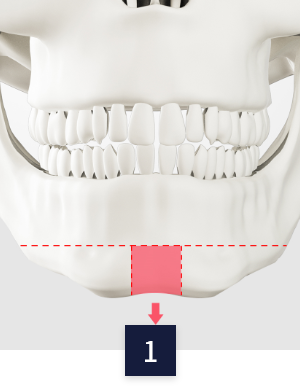

CASE 01

T절골

수술 방법

입안 절개

CT정밀검사로 턱 뼈와

신경선 파악 후 입안 절개

뼈 절제

중간의 턱 끝 뼈를

함께 절제

뼈 고정

나머지 절제된

뼈를 고정

이차각 정리

이차각을 정리하여

매끄러운 턱라인 완성

check-point

Check Point!

환자의 뼈 상태에 따라 노란색 부분의

뼈를 빼내어 높이를 줄일 수 있습니다.